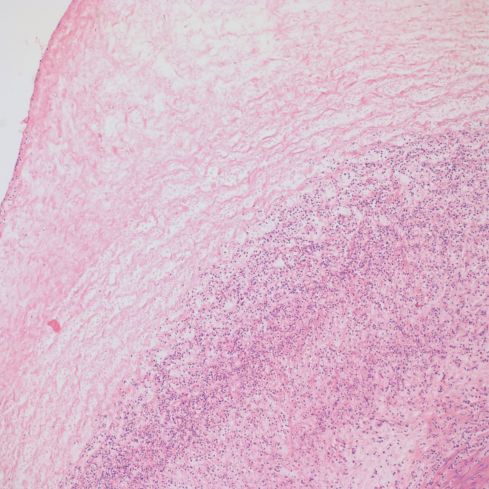

The most characteristic feature is the crescent of necrosis, often calcified, that is interposed between the umbilical surface and the vessel walls. Both arteries and vein are usually involved. Commonly there is acute funisitis, often with a gradient of viable neutrophils near the vessel leading to an accumulation of distal necrotic neutrophils (Fig 5).

Fig 5a) The basophilic rim of neutrophils and necrosis at low power.

Fig 5b) A medium power showing the inner basophilic band and an outer band of coagulation necrosis.

Fig 5c) A high power image showing basophilic neutrophils and debris, and then more superficial coagulation necrosis including neutrophils necrosis.